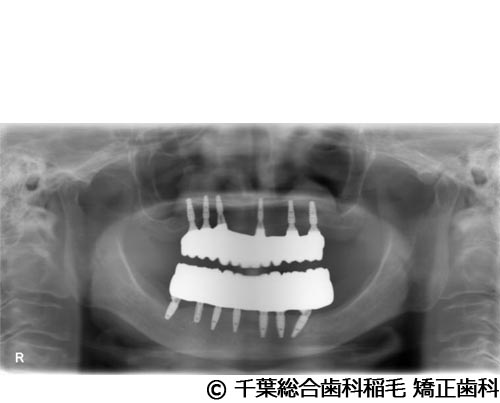

【症例5】All-on-6(オールオン6)

- 治療後

- 治療名

- All-on-6(オールオン6)

- 費用

- 7,500,000円(税込)

- 期間

- 10ヵ月

治療法

ご相談の結果、上顎はインプラントを6本、下顎は7本埋入し、All-on-6(オールオン6)という固定式のインプラント治療を行いました。

治療結果

入れ歯が動いてしまう煩わしさがなくなり、よく噛めるようになったと仰っています。

※治療結果は患者様によって個人差があります。